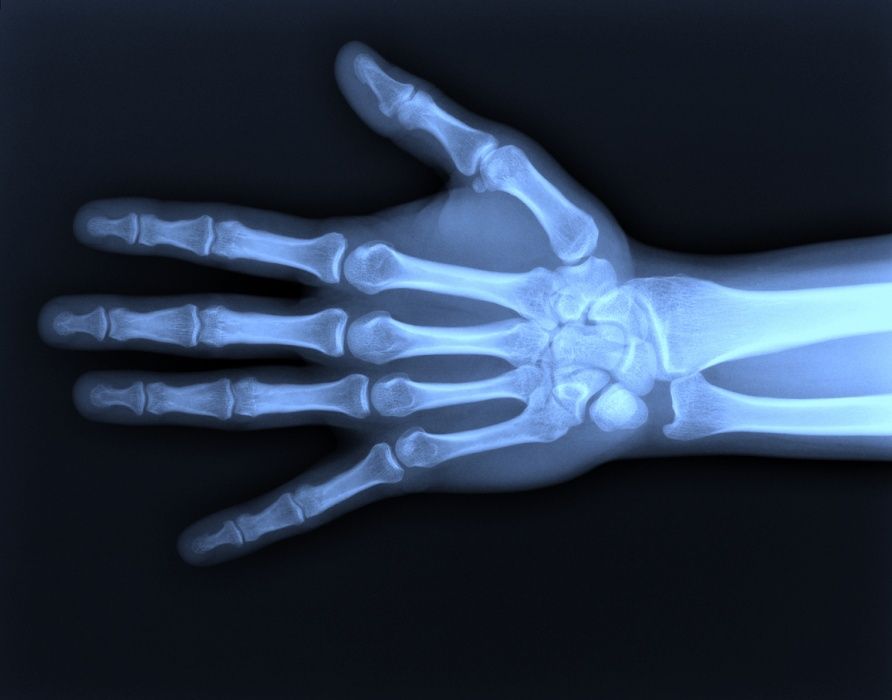

Im normalen Röntgenbild der Hand bleiben nicht-verschobene Kahnbeinbrüche oft unentdeckt. Indem eine spezielle Röntgenuntersuchung durchgeführt wird, lässt sich das Risiko weiter senken, einen Kahnbeinbruch zu übersehen. Bestehen beim als unauffällig diagnostizierten Röntgenbild weiterhin Zweifel, so sollte ergänzend eine Schnittbilduntersuchung (CT oder MRT) durchgeführt werden.